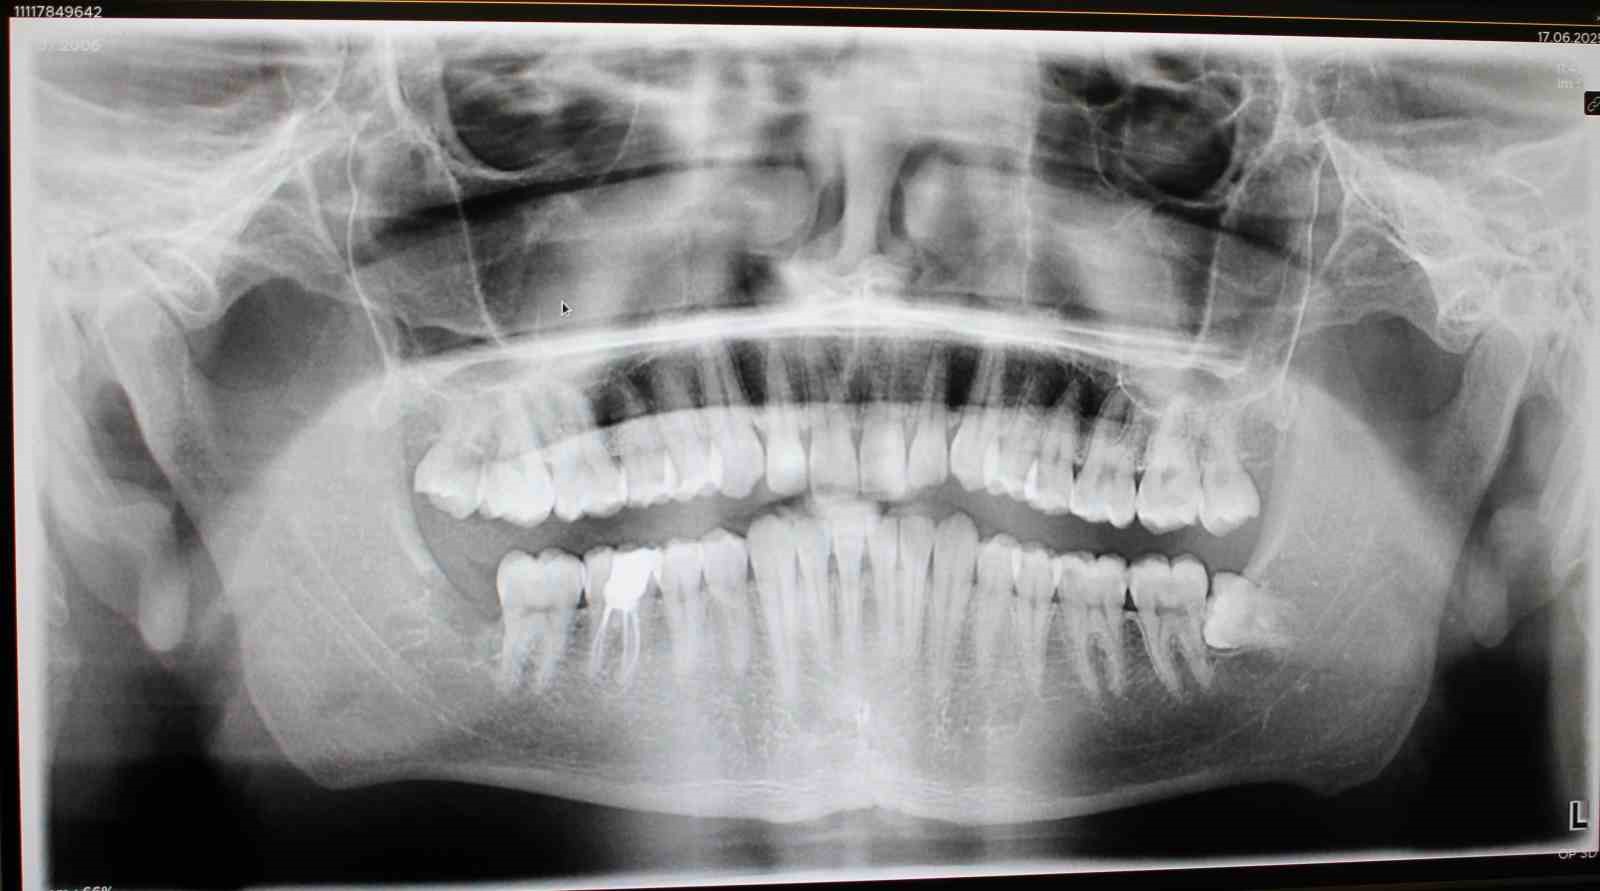

Midyat Ağız ve Diş Sağlığı Merkezi Başhekimi Dt. Yunus Deniz, Merkezde 21 aktif diş polikliniği bulunduğunu söyledi. Deniz, "Bunlardan biri ağız, diş ve çene cerrahisi polikliniğidir. Bu polikliniği açmamızın en büyük sebebi, vatandaşlardan gelen yoğun talepler ve sevk oranımızı sıfıra indirme hedefimizdir. Burada, hekimimiz tarafından gömülü 20 yaş dişleri, gömülü premolarlar, kanin dişler ve cerrahi kistik operasyonlar başarıyla gerçekleştirilmektedir. Bu hizmetlerin sunulmasına katkı sağlayan başta Sağlık Bakanlığı’mıza ve İl Sağlık Müdürlüğü’müze teşekkür ederiz. Midyatlı hemşehrilerimizin çevre illere gitmeden, kendi ilçelerinde tedavi olabilmeleri bizim için çok kıymetli. Bu süreçte özveriyle çalışan hekimimiz Agit Bilgiç’e ayrıca teşekkür ediyoruz. Kendisi bu hizmeti başlatarak elini taşın altına koydu ve Midyat halkı için önemli bir adım attı’’ ifadelerini kullandı.